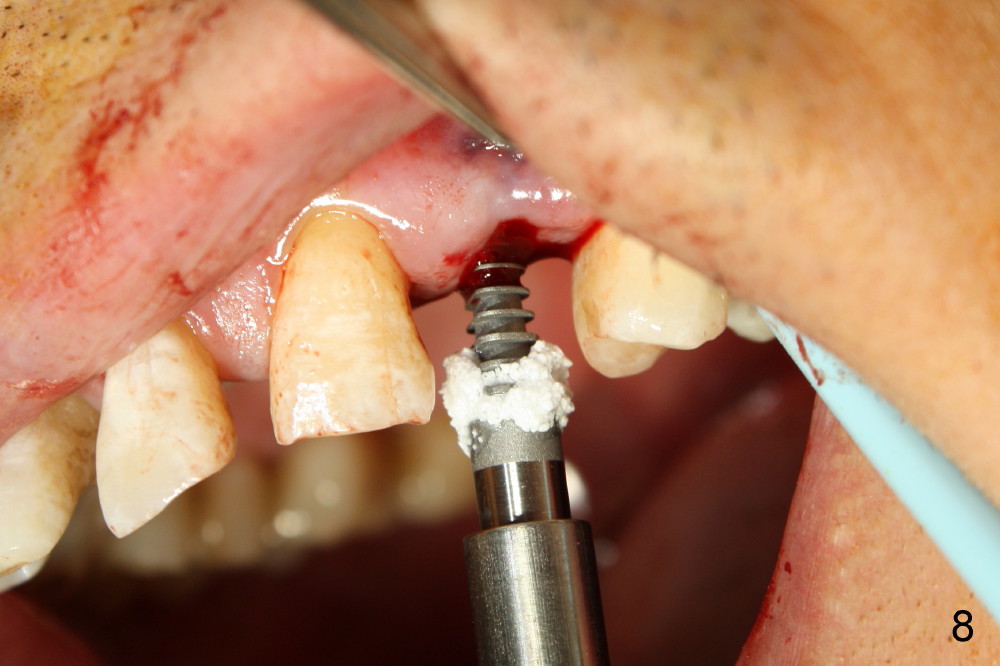

Dear Drs. Dunson and Borgner: Thank you for support. Fig.5 and 6 taken immediately prior to surgery show that the healing socket is elliptical (arrowhead). After D1 and D2 channel formers, D2 thin socket former is tapped in (Fig.7). The osteotomy needs to be redirected as shown by the black line. D2 implant is being inserted with Synthograft applied to the 1st two threads (Fig.8) and is in place (Fig.9,10). But the implant is not as stable as expected. There is a gap mesial to the implant (Fig.10 arrowhead), which is most likely created by re-directing the osteotomy with channel and socket formers.